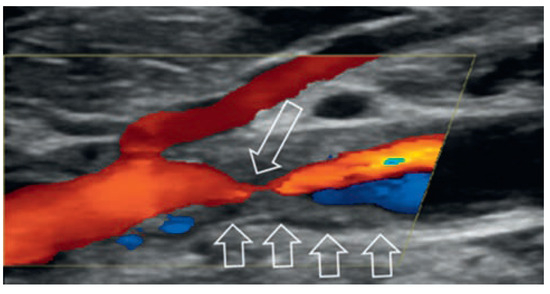

Case report A 22-year-old male experienced a presyncopal spell while studying for a university examination [...]